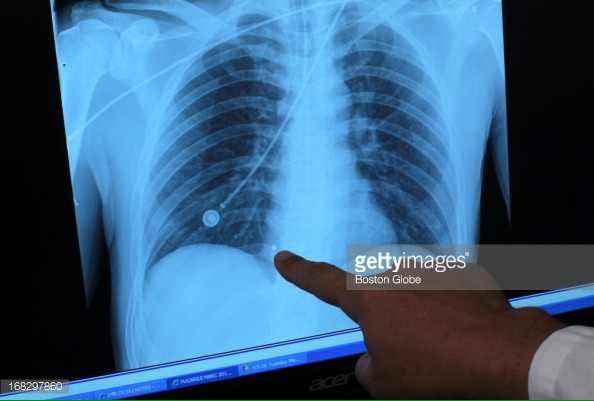

These came into evidence today; it's the BBs and shrapnel still embedded in Marc Fucarile's body. #Tsarnaev

CDTLzOcUMAEaISg.jpg

CDTLzOcUsAA2IsM.jpg

CDTLzOkUsAAopYZ.jpg

Jim Armstrong @JimArmstrongWBZ · Apr 23